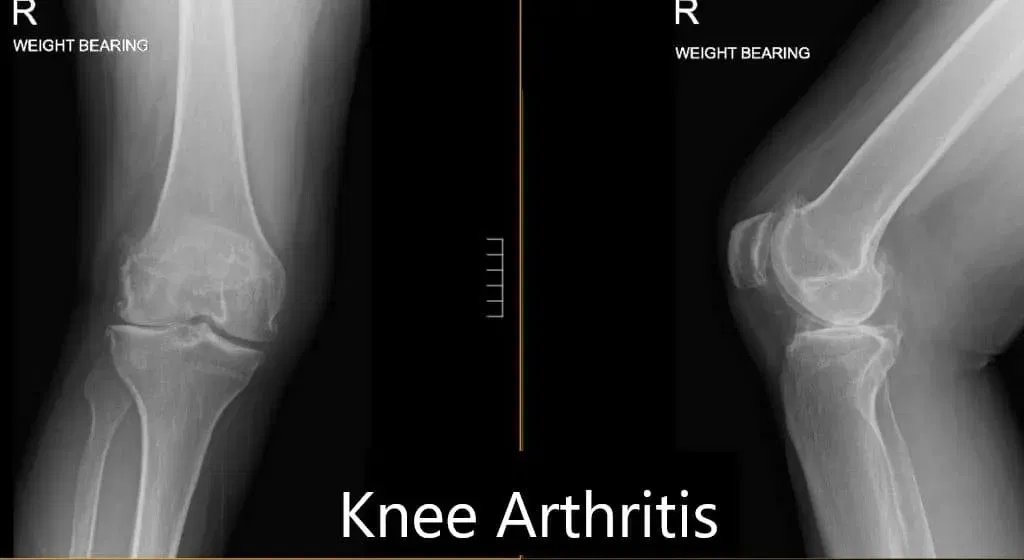

During the consultation and subsequent office visits the patient displayed extreme discomfort; Films revealed Moderate hypertrophic degenerative changes of the knee and patellar joint most prominently involved is lateral compartment. There are moderate osteoarthritic degenerative changes. Patient considered a Right TKA using a Conformis protocol. Patient revealed nor showed any additional medical conditions or complications and was overall healthy, making him a great candidate for surgery.